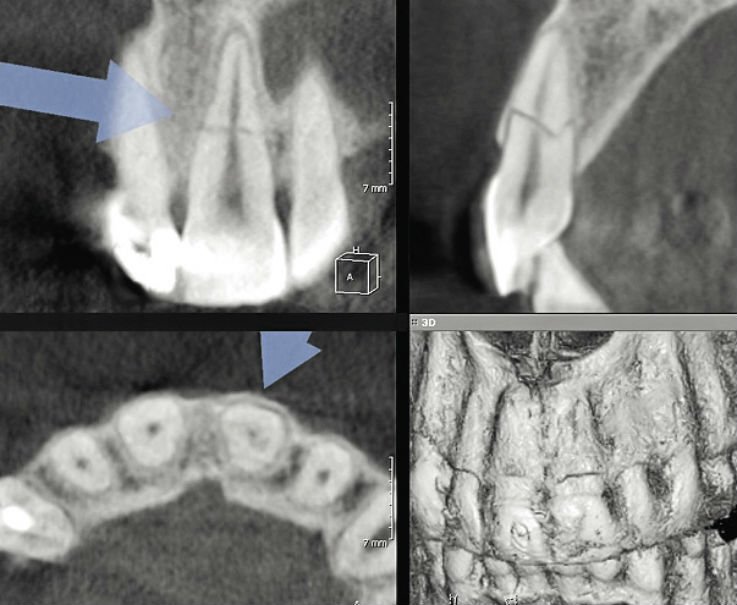

Рентгеновские снимки являются одним из самых важных инструментов в диагностике сломанного корня зуба. Они позволяют увидеть внутреннюю структуру зуба и определить, насколько глубоко произошло повреждение. С помощью рентгена стоматолог может оценить состояние корней, наличие воспалительных процессов и степень разрушения зуба.

3. Компьютерная томография (КТ)

В некоторых случаях, когда рентгенография не дает достаточной информации, может быть рекомендована компьютерная томография. Этот метод позволяет получить более детализированные изображения зуба и окружающих тканей, что помогает в более точной диагностике и планировании лечения.